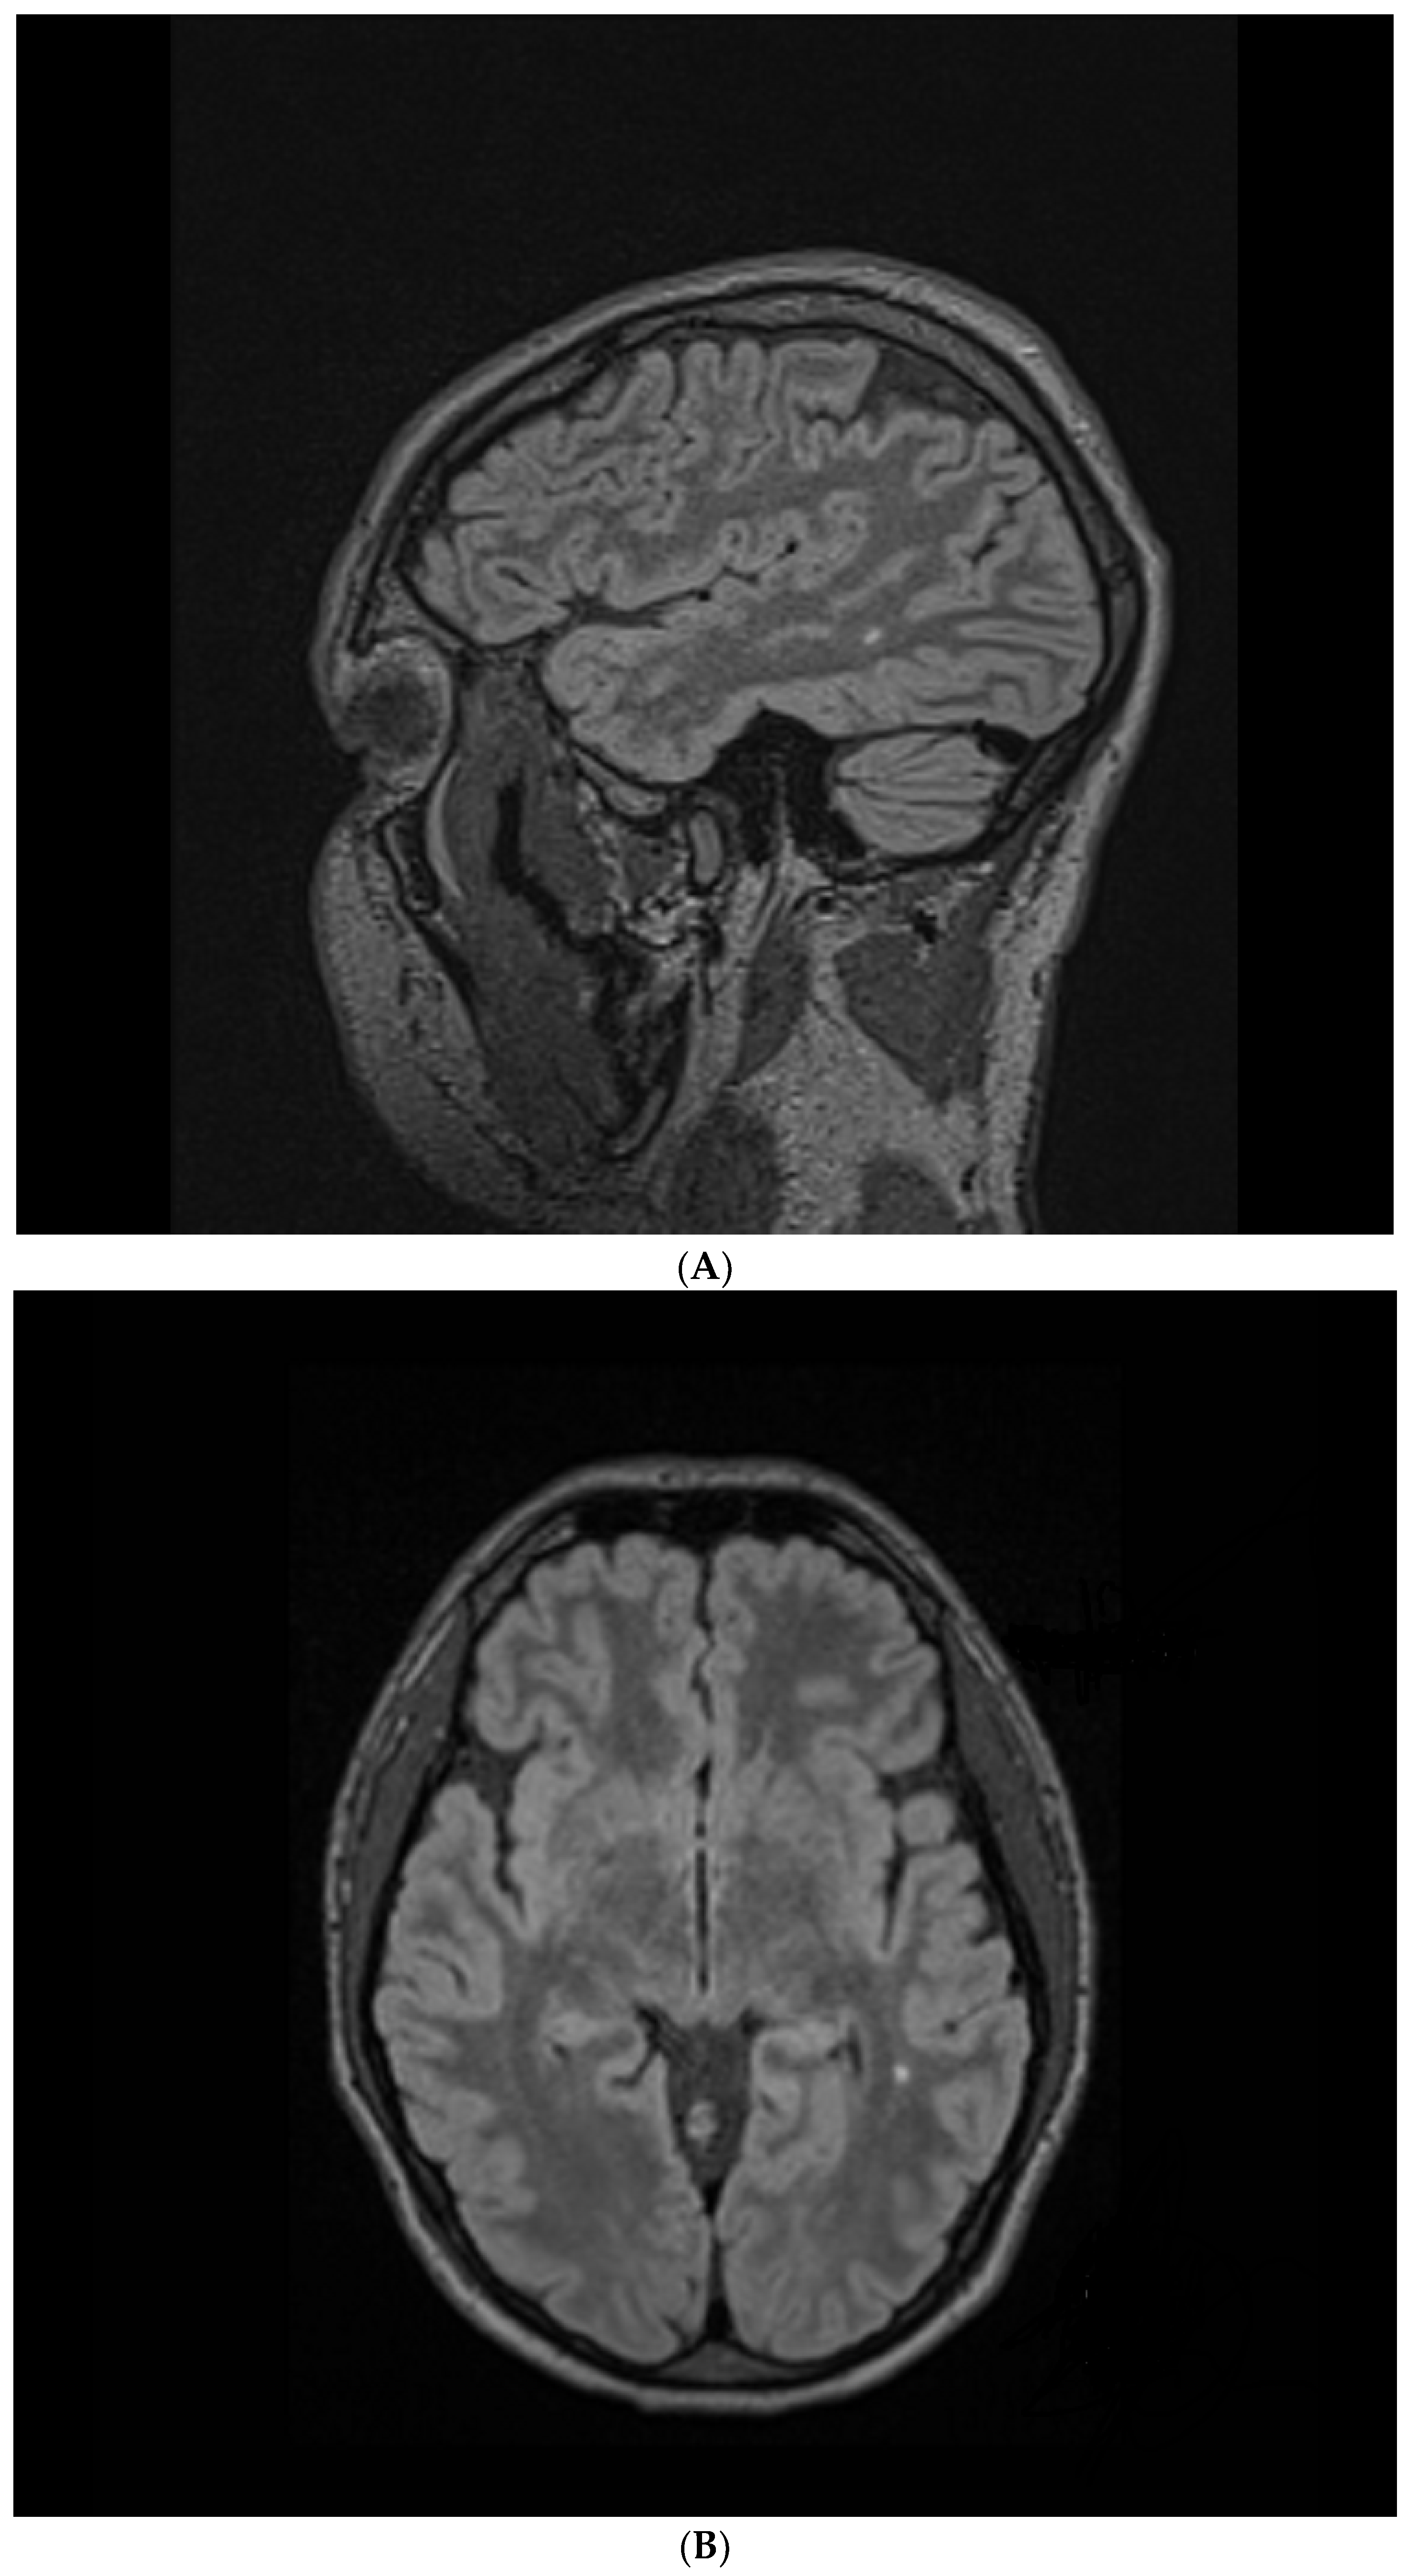

During the psychiatric treatment program, the patient was referred for a brain MRI which identified a new T2/FLAIR hyperintensity in the deep white matter of the left temporal lobe, measuring 3.3 × 2.0 mm (axial plane), of questionable clinical significance. One year later (age 25), the hyperintensity measured 3.6 × 2.3 mm (axial plane). A neurology consultant identified no neurological focal impairments, and excluded any intra-axial or extra-axial tumors. Five years later (age 30; Figure 2), the hyperintensity measured 4.0 × 3.0 mm (axial plane) and 5.4 × 3.3 mm (sagittal plane); 3-dimensional imaging was available only for the latter MRI.

Figure 2.

Anatomic magnetic resonance imaging (MRI) scans, using a 1.5 Tesla Siemens Avanto, without contrast. Repetition time (TR) = 6000 ms, echo time (TE) = 35.8 ms, matrix = 256 × 218 mm, number of excitations (NEX) = 186. (A) Sagittal Flair ISO, field of view (FOV) = 227 × 260 mm, slice thickness (SL) = 1.00 mm. (B) Axial Flair MPR, FOV = 260 × 260 mm, SL = 1.10 mm.